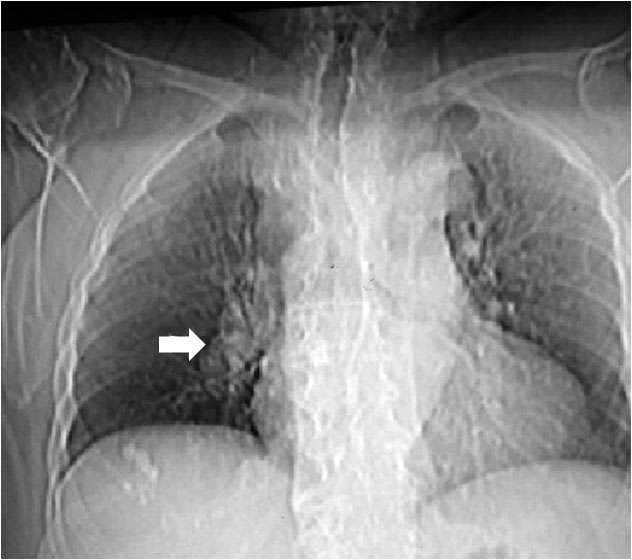

SIGNO DE LAS ASTAS DE CIERVO

Signo de hipertensión venosa pulmonar en la radiografía posteroanterior de tórax. Consiste en el engrosamiento de las venas de los campos pulmonares superiores (flechas) por redistribución del flujo, normalmente dirigido hacia las bases de forma preferente. Si la presión venosa pulmonar no se controla con este mecanismo fisiopatológico, se produce el edema intersticial y, finalmente, el edema alveolar.